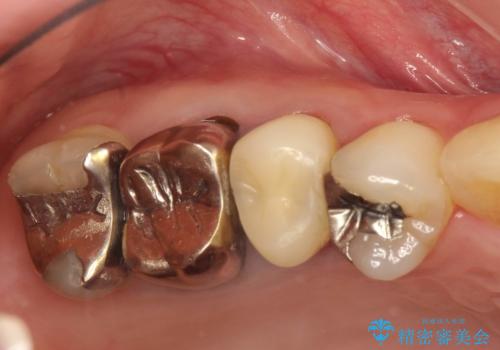

歯周外科・根管治療による長期予後を期待する奥歯の治療

- 歯周外科による歯肉・歯の相対的な位置関係の改善

詰め物の種類:e.max press In

かぶせ物の種類:PFZ Standard